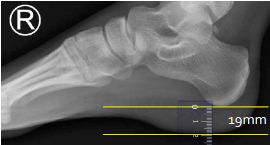

Q what is the name of this measurement? and what is the average + range?

A: Heel Pad Measurement

assesses the thickness of the heel pad. The average is 19 mm, with a maximum of 25 mm for males and 23 mm for females